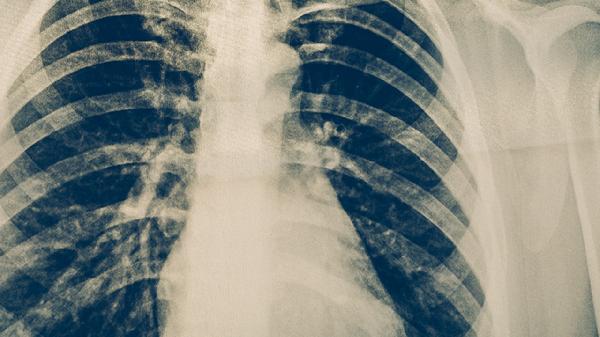

肺结核患者吃药期间不能熬夜,主要与药物代谢效率下降、免疫功能受损、治疗周期延长、耐药风险增加、症状加重等因素有关。抗结核药物需要规律作息保障药效,熬夜会干扰肝脏代谢并削弱免疫防御。

规范抗结核治疗需6-9个月,熬夜会延缓肺部空洞闭合速度。链霉素注射液的疗效与机体修复能力相关,睡眠紊乱可能造成病灶纤维化延迟,增加复治概率。